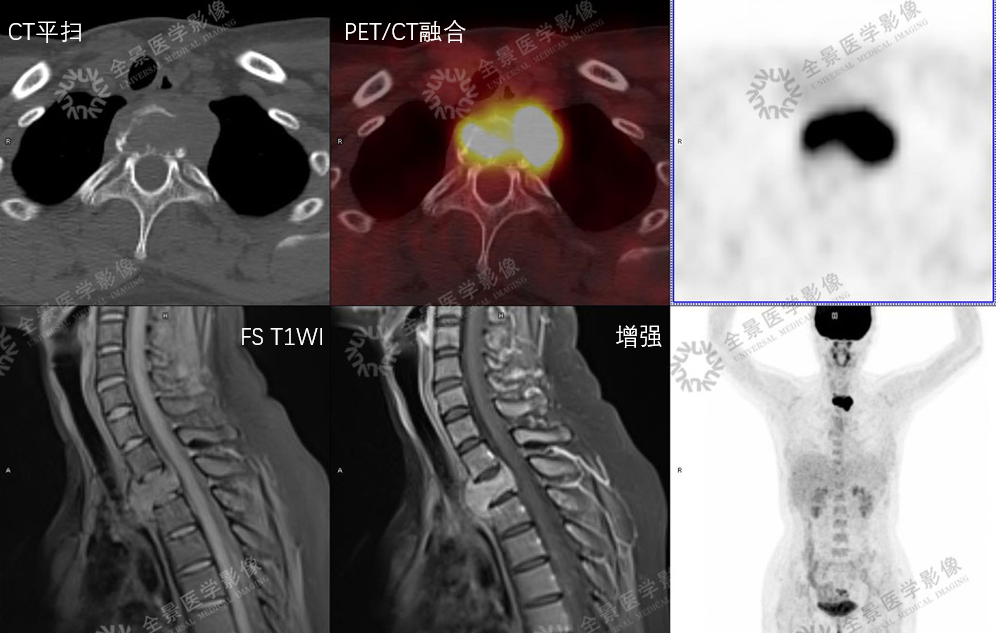

骨巨细胞瘤

T2WI不均匀等信号,PET/CT显示:软组织肿块,FDG明显摄取增高。

增强扫描明显强化